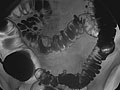

• In a double-contrast or air-contrast study, the colon is first filled with barium, and then the barium is drained out. This leaves only a thin layer of barium on the wall of the colon. The colon is then filled with air. This provides a detailed view of the inner surface of the colon. It makes it easier to see narrowed areas (strictures), diverticula, and swelling.

• If a double-contrast study is being done, the barium will be drained out and your colon will be filled with air.

Barium enema

One or more problems in the colon are found, such as:

• Polyps or growths on the inner wall of the colon.

• Sacs in the colon wall (diverticulosis).